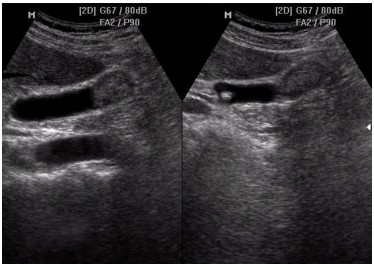

3.3.1. Siêu âm trước mổ

Siêu âm hiện nay là phương pháp chẩn đoán hình ảnh có nhiều ưu điểm: đơn giản, chi phí ít, không ảnh hưởng đến sức khỏe người bệnh, có độ chính xác cao. Tuy nhiên siêu âm cũng có những hạn chế như: khó khảo sát đường mật ở người béo, sỏi phần thấp OMC thì khó khăn hơn do bị hơi ở tá tràng - đại tràng ngang che lấp, bệnh nhân có sẹo mổ cũ, thành bụng dày...

Hình 3. Hình ảnh sỏi OMC đơn thuần trên siêu âm [5]

Siêu âm trong bệnh lý sỏi túi mật cho tỷ lệ chính xác từ 90-97% với độ nhạy từ 91-98%, độ đặc hiệu từ 94-100%. Đối với đường mật ngoài gan, tỷ lệ chẩn đoán đúng từ 68-98% [1], [3].

Siêu âm giúp xác định: Vị trí sỏi;Loại sỏi; Số lượng viên sỏi; Kích thước sỏi; Tình trạng đường mật; Tình trạng túi mật.